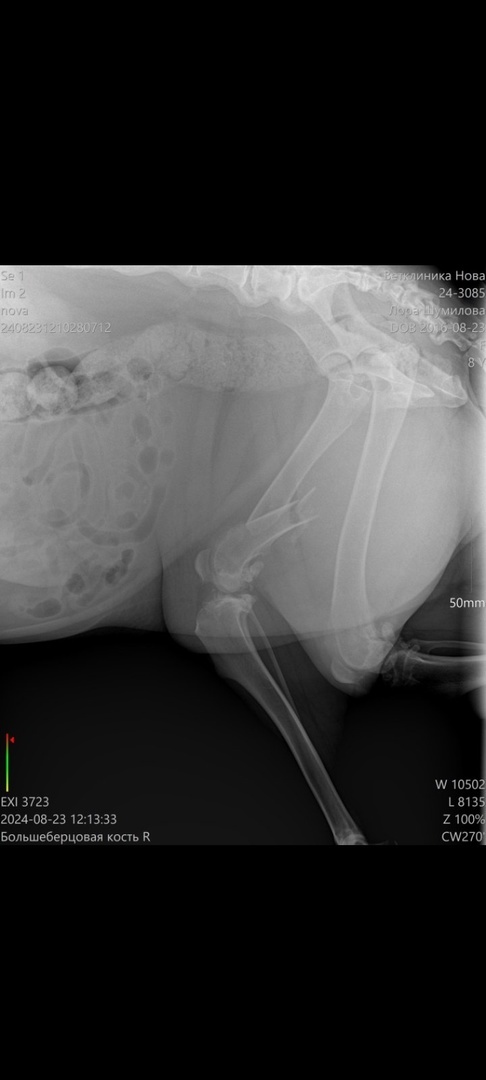

Дорогие друзья! Лоре нужна операция на лапку. У нее сломана большеберцовая кость. Всю жизнь живёт на улице. Домой так никто не забрал, хотя малышка ждала этого всю жизнь. А сейчас ещё и сбил самокатчик, теперь собака не может ходить. Лорочка испытывает страшные боли.

За ней приглядывают, кормят и обезбаливают, но этого недостаточно, собаке срочно трубуется операция. Для уличной собачки перелом это огромная беда. Друзья, если мы с Вами соберём 30 000 рублей, на следующей неделе собака уже будет прооперирована и лежать в стационаре на реабелитации. Это большой шанс для Лорочки.